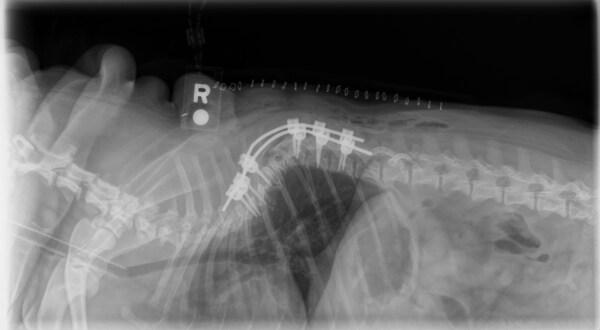

Canine Vertebral Stabilization |